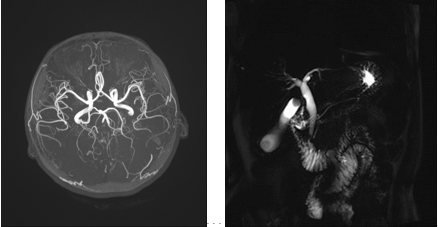

其他包括血管成像技术(MRA)、水成像(MRCP)、全身弥散(DWI)、磁敏感成像(SWI)以及3D高分辨神经系统解剖成像等。

CT血管造影(CTA):由手臂静脉快速推入对比剂后,通过人体血液循环,对检查部位的血管(动脉及静脉)进行三维立体成像的一种新的影像诊断手段。该技术具有无创、简便﹑快速等优势,能对全身血管及血管相关性疾病做出有效的诊断。